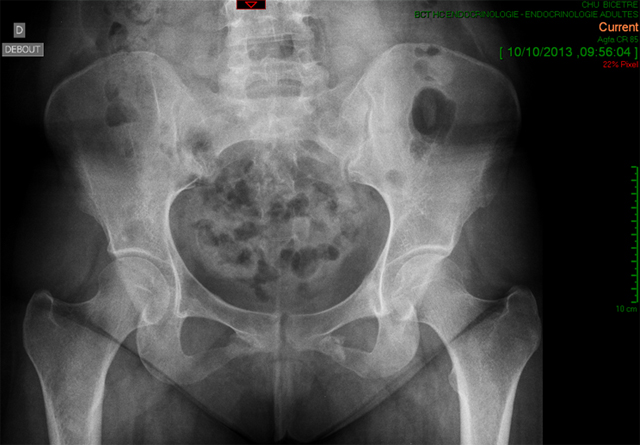

Cas clinique N°68

Dr Véra Lemaire Paris

Diagnostic et analyse des réponses

Bien sûr la patiente mesurait 1m70 ; l'IMC à 28 était le bon. Toutes mes excuses.

Comme la grande majorité des lecteurs l'a diagnostiqué, il s'agissait d'un syndrome de Cushing cliniquement évident avec prise de poids, vergetures et hyperTA modérée révélé, ce qui est exceptionnel par des fractures spontanée des branches ischio-pubiennes alors que l'ostéoporose est banale.

Le scanner surrénalien montrait